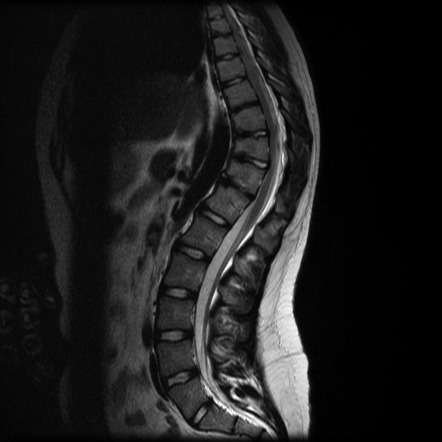

- Chụp cộng hưởng từ (MRI) và chụp CT: Đánh giá chi tiết tủy sống và loại trừ nguyên nhân khác gây cong vẹo cột sống.